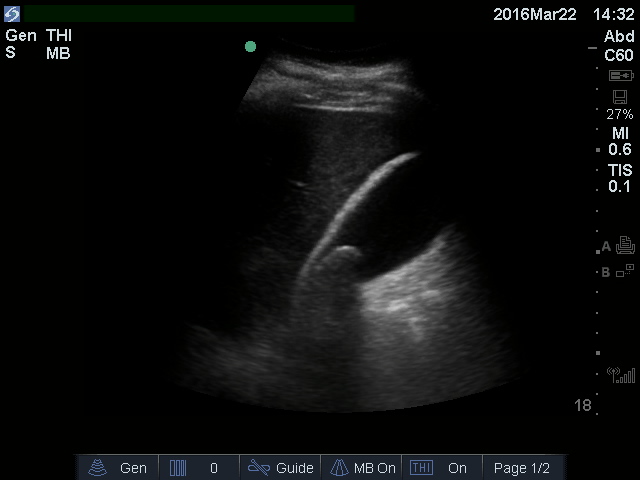

• Figure 1-GB single stone neck.jpg

• Figure 1: Solitary stone in gallbladder neck